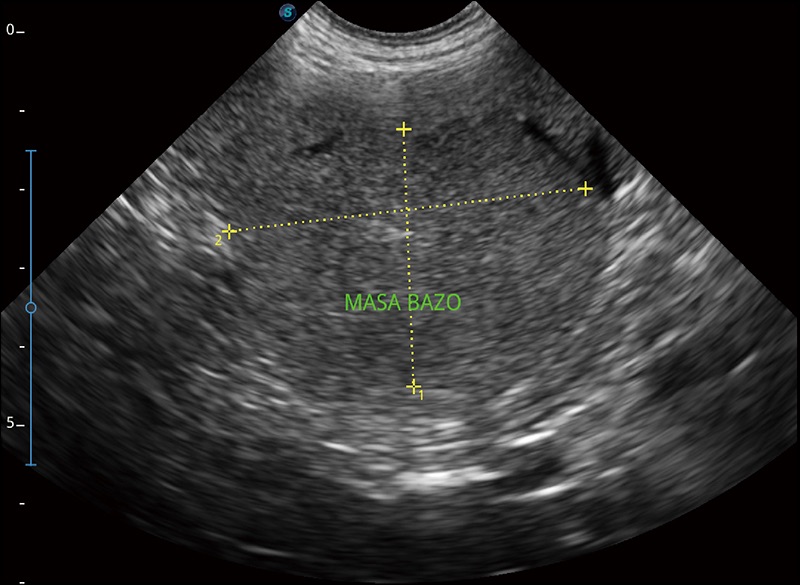

α1卓越的图像质量和便捷的工作流程,使每位宠物医生都能轻松扫查。其全面的兽用应用功能和紧凑型的结构设计,可以满足动物检查的多种需要。专业的预设检查模式和多领域测量软件包有助于为不同类型的动物提供检查, 让宠物医生能够出色的完成工作。

穿刺针增强

高清显示穿刺进针情况